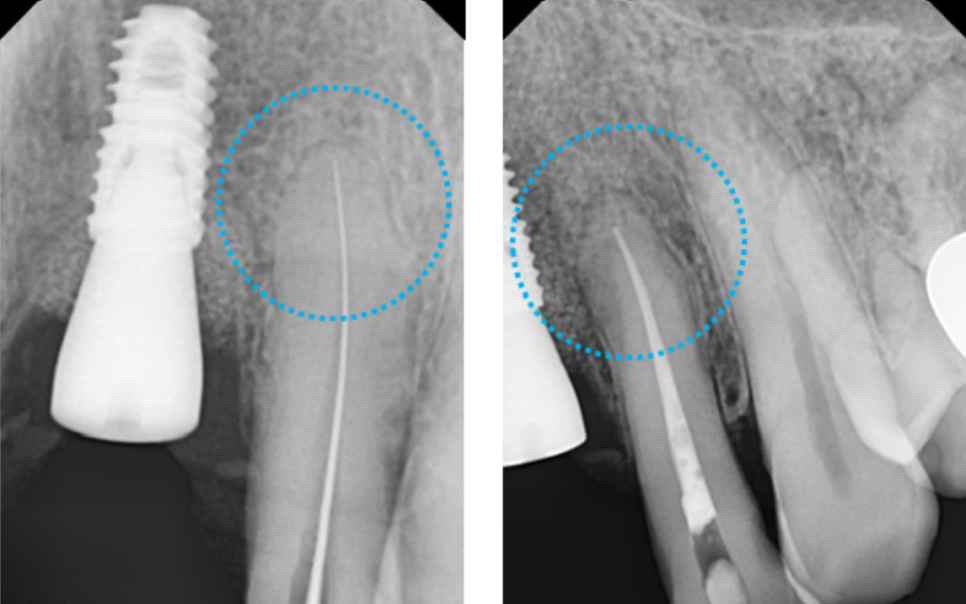

확대해서 보는 치근단 엑스레이 보시면,

하얗게 뿌리부분에 신경치료 재료가 잘 들어가

잘 마무리 된 것을 볼 수 있습니다.

본뜨는 나사를 연결해서 인상을 채득하면,

이렇게 기공소에서 맞춤 어버트먼트로 제작이됩니다.